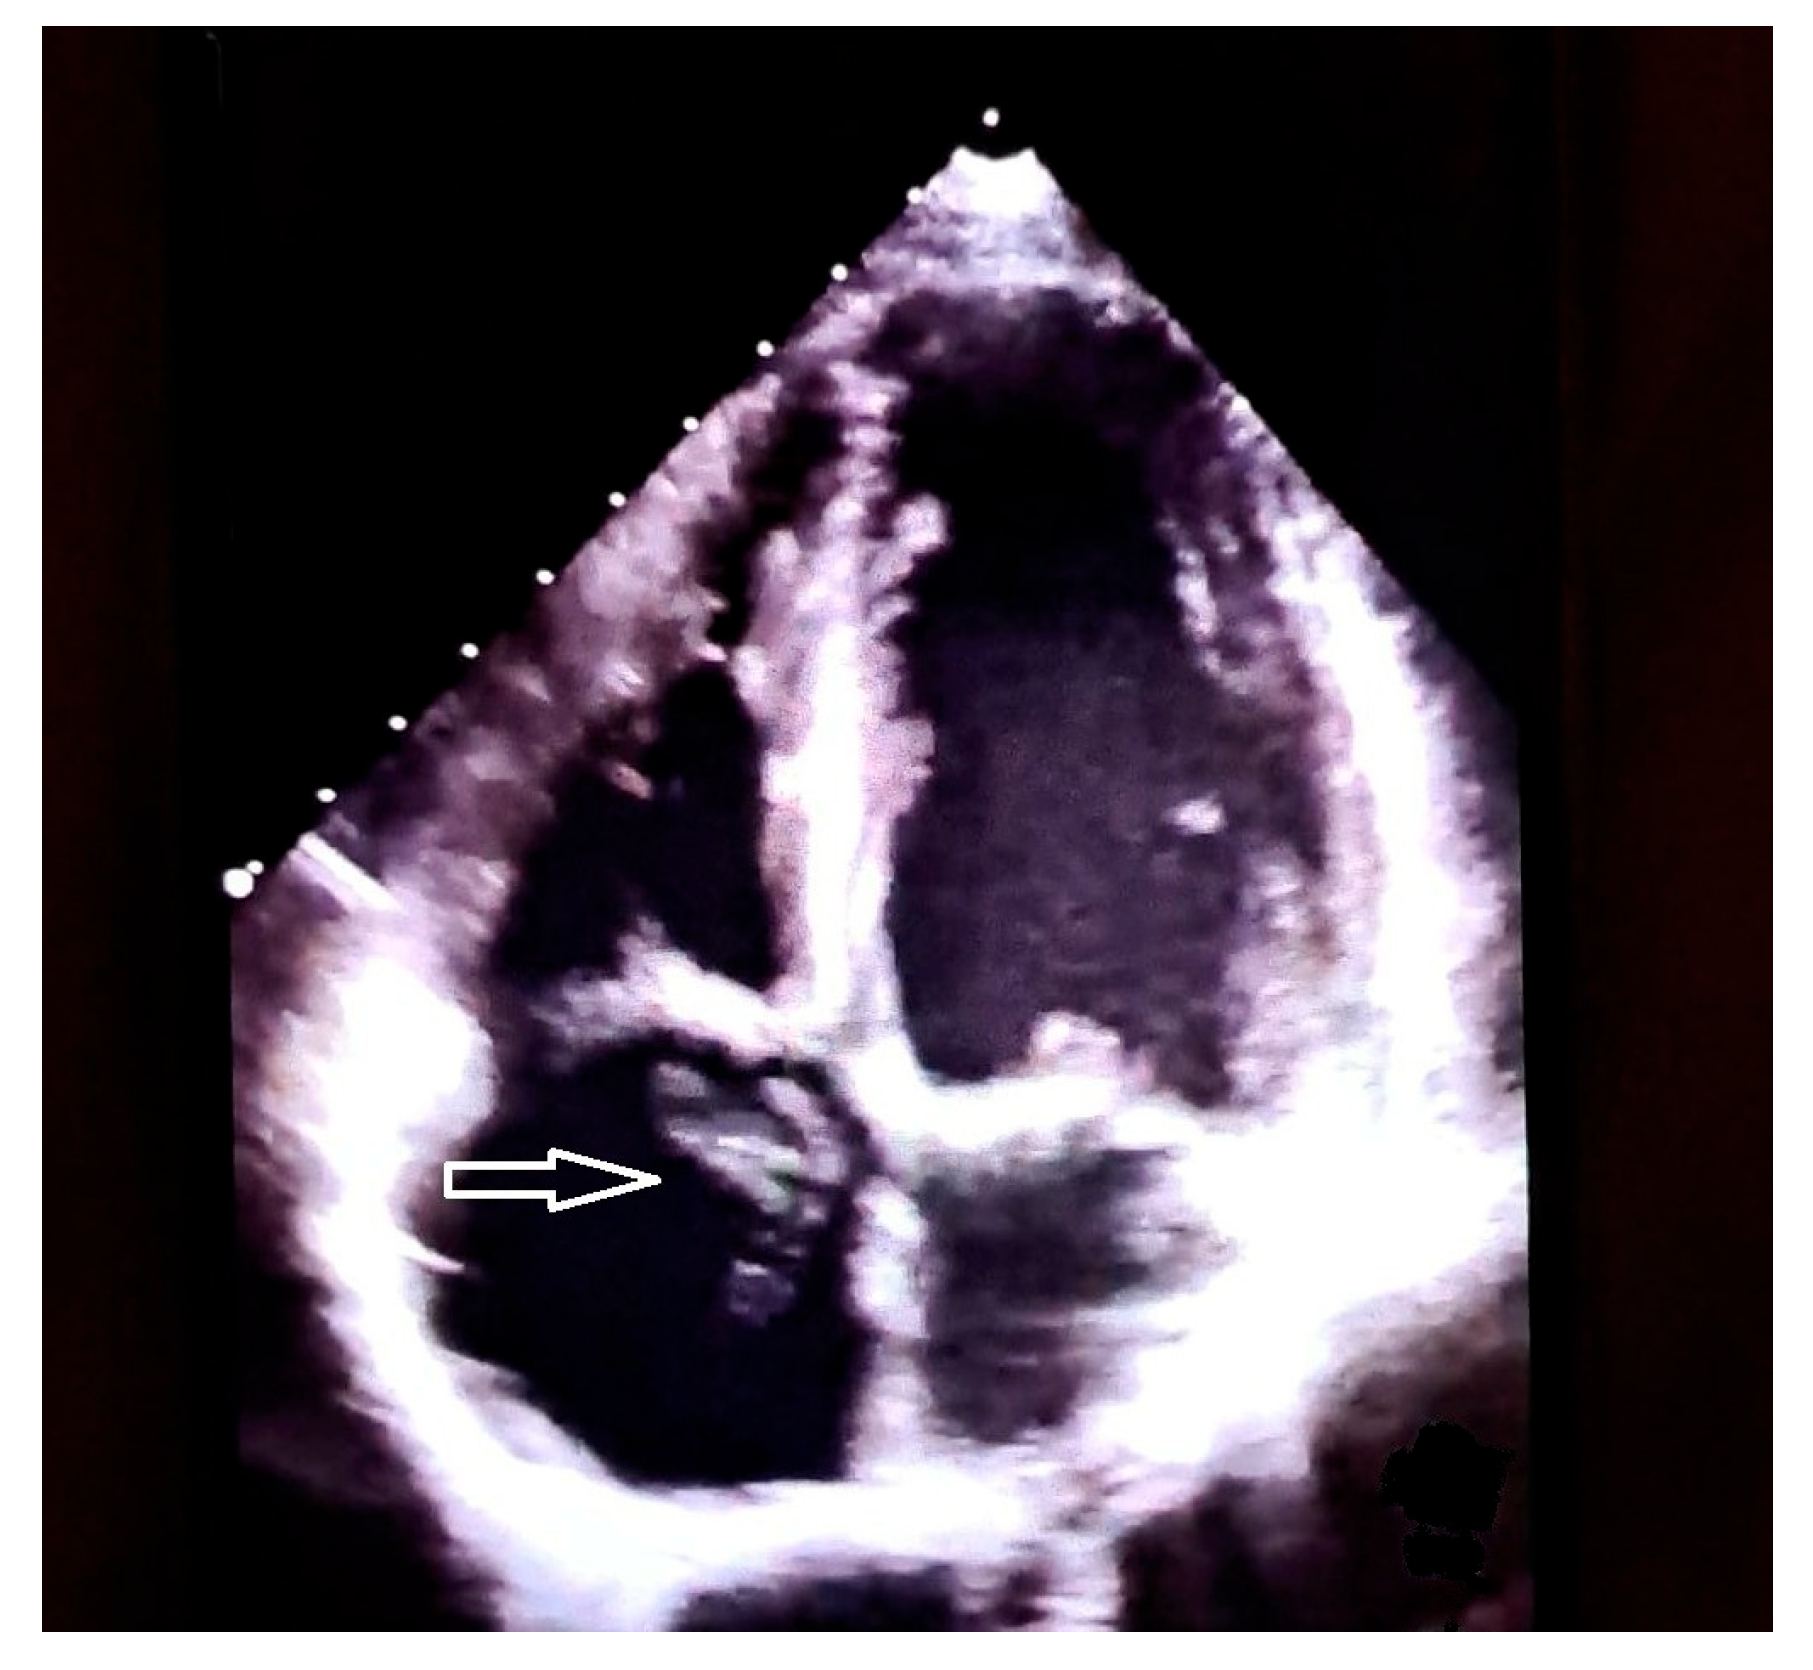

- Sozzi, F.B.; Montanaro, C.; Bacà, L.; Viani, G.M.; Zilocchi, M.; Canetta, C.; Meazza, R.; Pavone, L.; Lombardi, F. Cor Triatriatum Dexter Associated with Atrial Septal Defect: Management in a Complex Clinical Case. Echocardiography 2017, 34, 1725–1729. [Google Scholar] [CrossRef]